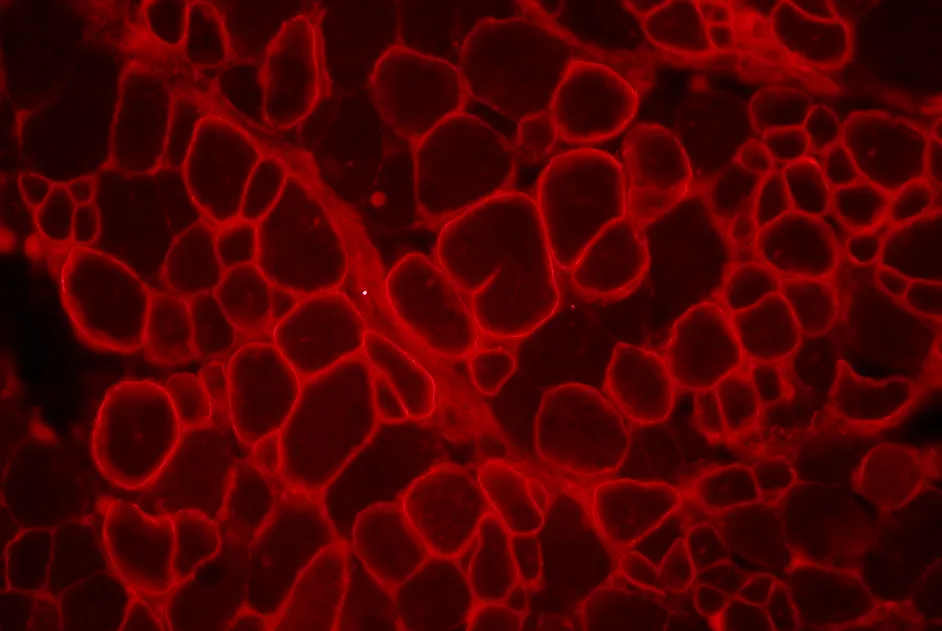

Généthon renforce sa collaboration avec la société de biotechnologie américaine Sarepta Therapeutics pour le développement de son produit de thérapie génique pour la myopathie de Duchenne. Après un premier accord en 2017 visant à finaliser le développement pré-clinique, le nouvel accord ouvre la voie à un essai clinique pour 2020.